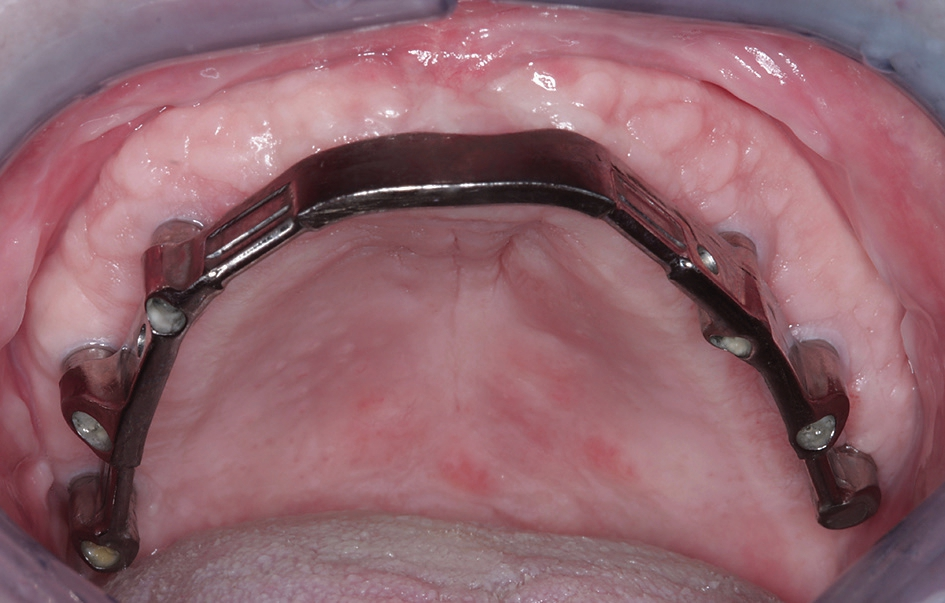

Im vorgestellten Fall wurde der Steg aus Titan gefertigt. Zurück im Praxislabor wird der fertige Steg bei perfekter Passung auf dem Meistermodell verschraubt und darauf die endgültige Sekundär- und Tertiärstruktur angefertigt. Bei dem hier vorgestellten Patientenfall wurde das Sekundärgerüst herkömmlich gegossen (Brealloy, Bredent GmbH, Senden) und die Arbeit mit lichthärtendem Kunststoff und Konfektionszähnen komplettiert, wobei die Ästhetikanprobe unverändert übernommen wurde.

Die Passung der definitiven Restauration wurde im Mund des Patienten mithilfe des Sheffield-Testes überprüft, mit dem die Passgenauigkeit einer primär verblockten Mesio-Struktur überprüft werden kann. Hierbei wird nach Aufsetzen der Mesio-Struktur jede einzelne Halteschraube separat angezogen, ohne die jeweils anderen zu aktivieren. Dies dient der exakten Überprüfung einer präzisen Passung, da bei ungenügender Passgenauigkeit bei Anziehen nur einer Schraube eine Kippung und Spaltbildung am Gerüst auftreten würde, welche röntgenologisch zu erkennen ist.

Nachdem die Passung und Ästhetik der fertigen Arbeit erneut von Behandler und Patientin überprüft worden waren, konnte die Arbeit definitiv eingesetzt werden (Abb. 26 und 27). Anschließend wurde die Patientin in den Gebrauch der Riegelvorrichtung eingewiesen sowie über die Mund- und Prothesenpflegemaßnahmen aufgeklärt (Abb. 28). Durch die Einbindung des Patienten in ein halbjährliches Recallprogramm kann in regelmäßigen Abständen der Sitz der Konstruktion und der periimplantäre Zustand überprüft werden.